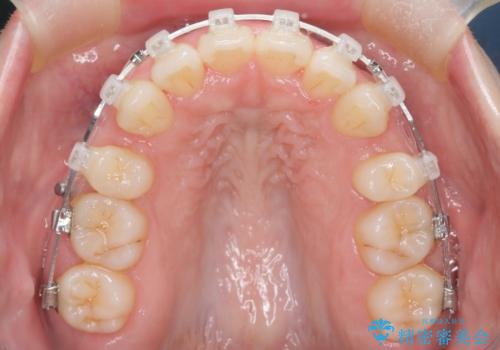

- 矯正装置

- 審美装置

抜歯スペースの移動量を調整するために、矯正用アンカースクリューや親知らずを活用して治療を行いました。